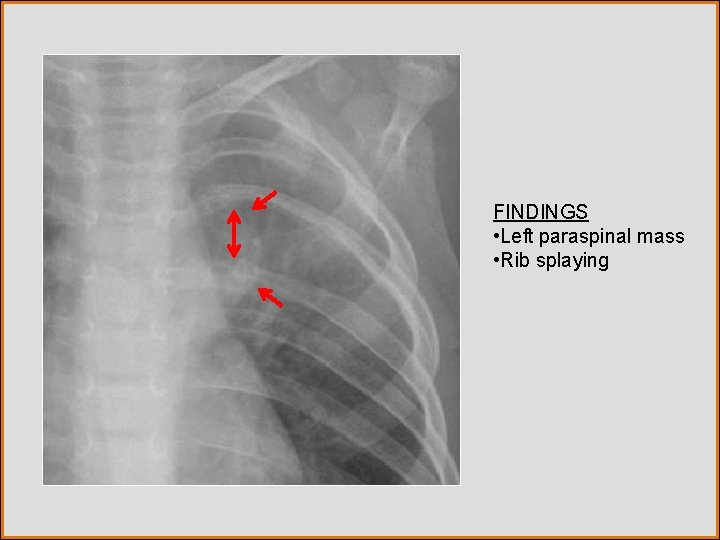

Test Your Diagnosis Which feature(s) is(are) present? a. Alveolar opacity b. Rib splaying c. Paraspinal mass d. Ectatic aortic arch

FINDINGS • Left paraspinal mass • Rib splaying